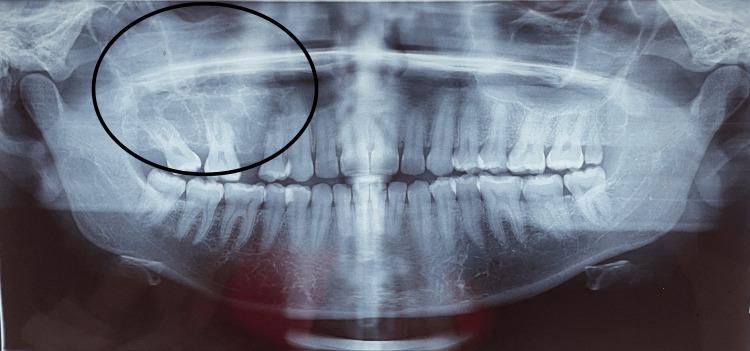

Odontogenic fibromyxoma typically presents as painless swelling in the jaw, and clinically, it grows slowly, becoming benign and asymptomatic. It causes the cortical plates to expand gradually, which leads to mobility and drifting of the teeth. Root resorption is also common. The tumor is locally aggressive in nature. It is also known to have a high recurrence rate. We present the case of a 30-year-old female patient who was diagnosed and treated for odontogenic fibromyxoma of the maxilla conservatively with enucleation. The radiograph showed a multilocular lesion, which can be confused with ameloblastoma, aneurysmal bone cyst, or odontogenic keratocyst. Hence, with proper clinical, radiographic, and histopathological examination, a correct diagnosis can be made and adequate treatment can be planned.

牙源性纤维黏液瘤通常表现为颌骨无痛性肿胀,临床上生长缓慢,呈良性且无症状。它导致皮质骨板逐渐扩张,进而引起牙齿松动和移位。牙根吸收也很常见。该肿瘤本质上具有局部侵袭性,且已知复发率高。我们报告一例30岁女性患者,她被诊断为上颌骨牙源性纤维黏液瘤,并通过摘除术进行了保守治疗。X线片显示为多房性病变,可能与成釉细胞瘤、动脉瘤样骨囊肿或牙源性角化囊肿相混淆。因此,通过适当的临床、影像学和组织病理学检查,可以做出正确诊断并制定适当的治疗方案。